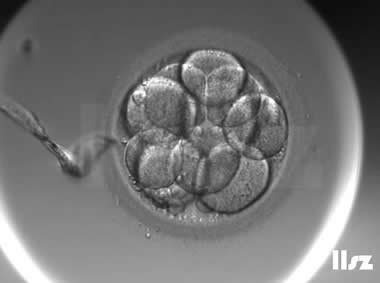

下面视频是胚胎在时差培养箱中培养至D3的整个过程,图片是D3(第68小时)的卵裂期胚胎图,本文D3胚胎评价是以D3时间点图片的形态学为依据,胚胎评级如下:

| Ⅱa级:该枚D3胚胎为9细胞,碎片不超过10%,因此评级为Ⅱa级。 | |